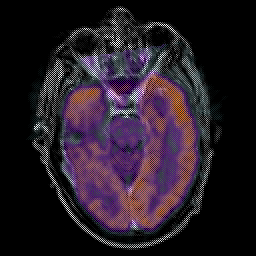

Glioma Overlay -- Slice #7

[Home][Help][Clinical] Slice 7